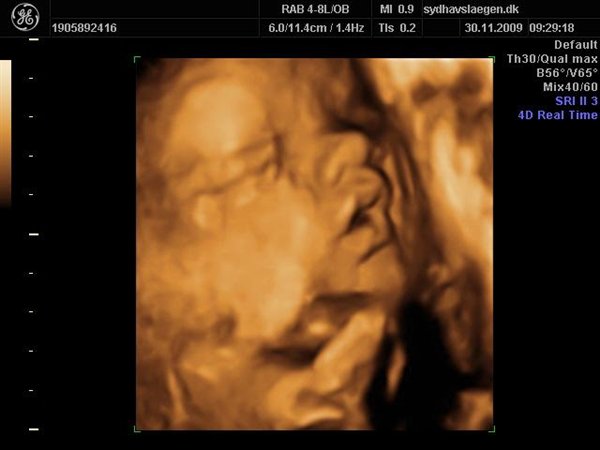

Vi skal give 1400 kr for 45 minutters total gennem scanning, hvor hun fortæller, undersøger babyen fra top til tå, laver vægtskøn også får vi billeder og dvd med hjem.... Og ja det er da mange penge, men min forlovede har haft en masse vikar timer den her mdr, også sagde han at han syntes vi skulle bruge de penge på noget vi normalt ikke ville have gjort. Han sagde egentlig at jeg kunne gå ud og shoppe for dem, men jeg har termin om ti uger, så gider ærlig talt ikke bruge penge på nyt graviditets tøj, så hellere det her som vi egentlig havde valgt fra pga prisen, men som vi begge to rigtig gerne vil....